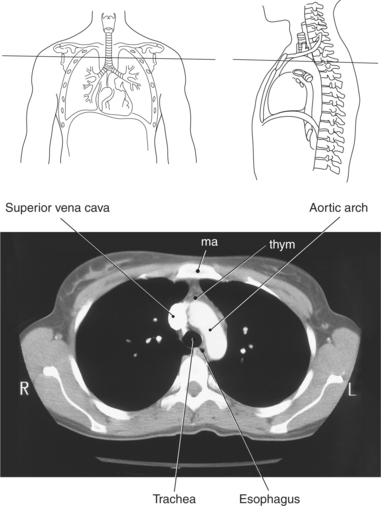

The mediastinum is the midline region of the thoracic cavity located between the two pleural cavities of the lungs. It extends from the superior thoracic aperture to the diaphragm and is bordered anteriorly by the sternum and posteriorly by thoracic vertebrae. The mediastinum can be subdivided into compartments for descriptive purposes. The superior and inferior compartments are made by drawing an imaginary line between the sternal angle and the intervertebral disk of T4-T5. The superior compartment constitutes the upper portion of the mediastinum. It contains the thymus gland and acts as a conduit for structures as they enter and leave the thoracic cavity. The inferior compartment can be further divided into anterior, middle, and posterior compartments (Figure 6.23). The anterior compartment is located anterior to the pericardial sac and posterior to the sternum. The middle compartment is the area that contains the pericardial sac, heart, and roots of the great vessels. The posterior compartment is the area lying posterior to the pericardium and anterior to the inferior eight thoracic vertebrae. Structures located within the mediastinum include the thymus gland, trachea, esophagus, lymph nodes, thoracic duct, heart and great vessels, and various nerves.

The thymus gland is a triangular-shaped bilobed gland of lymph tissue, located in the superior portion of the mediastinum just behind the manubrium (Figures 6.24 through 6.26). It is considered the primary lymphatic organ responsible for the development of cellular immunity. T-lymphocytes within the blood reach the thymus as stem cells, where they are stored while they undergo T-cell differentiation and maturation. The thymus gland produces a hormone, thymosin, that is responsible for the development and maturation of lymphocytes. The thymus gland reaches its maximum size during puberty and gradually diminishes in size in the adult.

Throughout its course in the mediastinum, the trachea runs anterior to the esophagus. In cross section, the trachea appears as a round air-filled structure to the point at which it bifurcates at the carina (Figures 6.9 and 6.18). The esophagus appears as an oval-shaped structure that descends through the diaphragm to enter the stomach at the gastroesophageal junction (Figures 6.27 and 6.28).